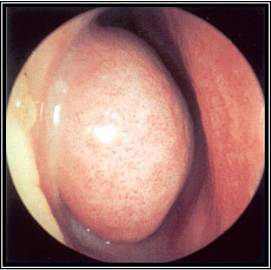

The nasal cavity should be examined for the presence of mucosal erythema or purulent discharge. Optimal examination is performed after topical decongestant spray.[18] Either an otoscope or a nasal speculum and head light may be used. However, because nasal examination may be difficult or the signs non-specific, nasal endoscopy is recommended in selected patients, including patients refractory to empirical antibiotic therapy or where there is concern for antibiotic resistance, or in immunocompromised patients.

Endoscopy can provide excellent visualisation of the nasal cavity and sinus drainage paths. There are two types of endoscope: rigid and flexible. A rigid nasal endoscope has superior resolution and only requires the use of one hand. This easily allows cultures of the nasal cavity or sinus to be obtained if necessary. A flexible nasal endoscope is more comfortable for patients, but requires both hands to use. There are flexible nasal endoscopes that have a channel for collecting cultures, but these tend to be larger and more uncomfortable and they are also more difficult to re-process. Generally, the flexible nasal endoscope is preferred in children as it is better tolerated; however, either type may be used in adults and children. Choice will depend on the practitioner's familiarity with the procedure, and most will be performed by an ear, nose, and throat specialist.

[Figure caption and citation for the preceding image starts]: Nasal endoscopy of the left nasal cavity showing a small polyp and pus in the middle meatusFrom the collection of Joseph K. Han [Citation ends].